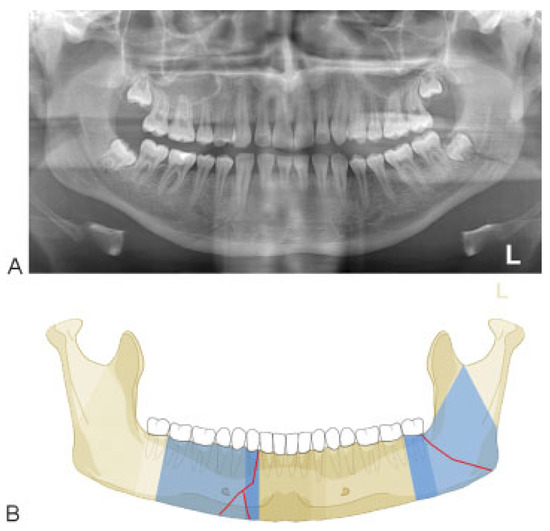

Symphysis/Parasymphysis Region

Mandibular Body Region

Case Examples

Appendix A. Additional level 2 coding examples of mandibular fractures